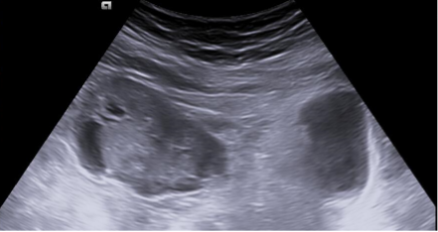

Compresión extrínseca de la vejiga por tumoración mixta solidoquística que proceden de zona anexial derecha, en zona superior y lateral derecha.

La ecografía abdominal es una herramienta muy útil para el Médico de Familia y permite adelantar el tiempo diagnóstico y el inicio del tratamiento de la patología subyacente. En este caso, gracias a la realización de una ecografía clínica en el centro de salud, se pudo objetivar una masa anexial derecha, causante de la sintomatología, y de esta forma iniciar el tratamiento de una forma precoz.